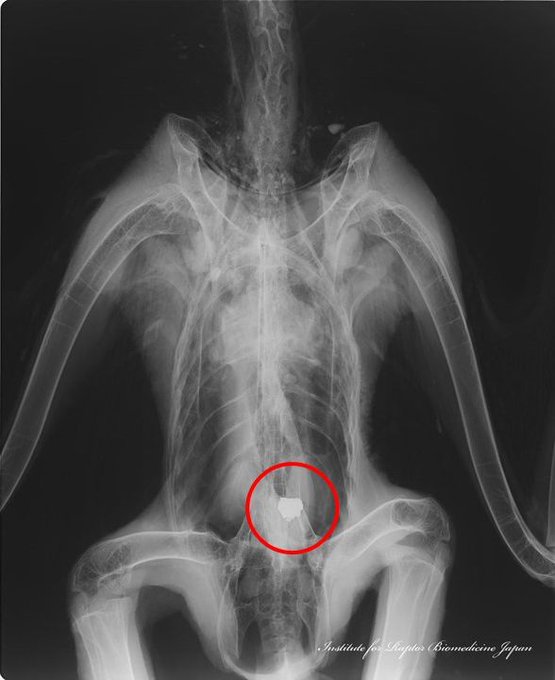

鉛弾に被弾した獲物の肉を食べ、鉛片を誤食して発症する猛禽類の鉛中毒。X線写真には鉛ライフル弾の砕片や塊、鉛サボット弾等が写る事がある。鉛片が無いが血中鉛濃度が高いことも多い。鉛が吸収されている場合だが、血液や臓器の鉛安定同位対比分析で多くが鉛ライフル弾に起因することがわかっている

狩猟後に放置されたエゾシカの死体(狩猟残滓)を食べ、肉とともに鉛弾を飲み込んで鉛中毒死したオオワシ2症例。

① 1番目と2番目の写真は、鉛ライフル弾を摂食した個体のレントゲン写真と摘出した鉛弾。

② 3番目と4番目は散弾銃(ハーフライフル)用サボット弾(スラッグ弾)を飲み込んだ症例。